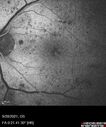

Macular ischemia left eye in type I diabetic (enlarged foveal avascular zone)213 views29 year old female with type I diabetes since age 5. Left eye has enlarged FAZ with vision of 20/20 OD and 20/60 OS. Both eyes have CSME. The left eye did have focal laserApr 12, 2023